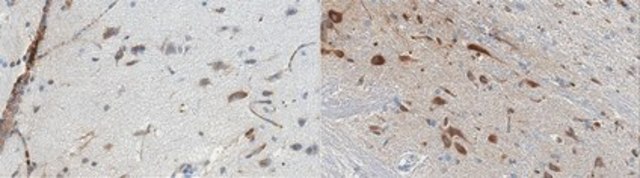

Immunohistochemistry Analysis: A 1:50-250 dilution from a representative lot detected serotonin receptor 1B in human (cerebellum and cerebral cortex) and rat (cerebral cortex and medulla) brain tissue sections.